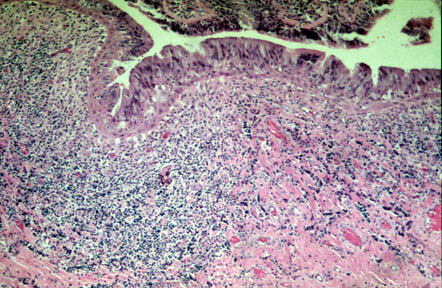

- Chronic, necrotizing infection of bronchi in a segment or multiple segments of

the lung.

- Infection damages and weakens walls of bronchi so that these

structures become markedly dilated

and filled with mucous and pus.

- The chronic infection damages the integrity of the bronchial wall causing

dilatation.

- Saccular bronchiectasis

follows destructive inflammation of the bronchial wall.